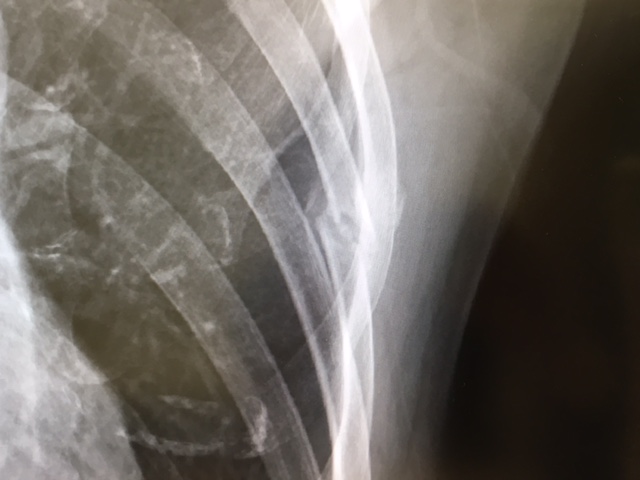

↓こちら、骨折直後。

パソコンのカーソルがあるところが5番目の肋骨で、見事にポッキリ・・・はい、折れてますねと。実は、このときにはわかりませんでしたが、右隣の4番目にも亀裂が入っていたもよう。当時は、くしゃみなどの特定の動作をした時に激痛。胸にゴムバンドみたいなものを巻いて動きを制限しつつ、鎮痛剤を飲み、湿布を貼って過ごす(涙)。